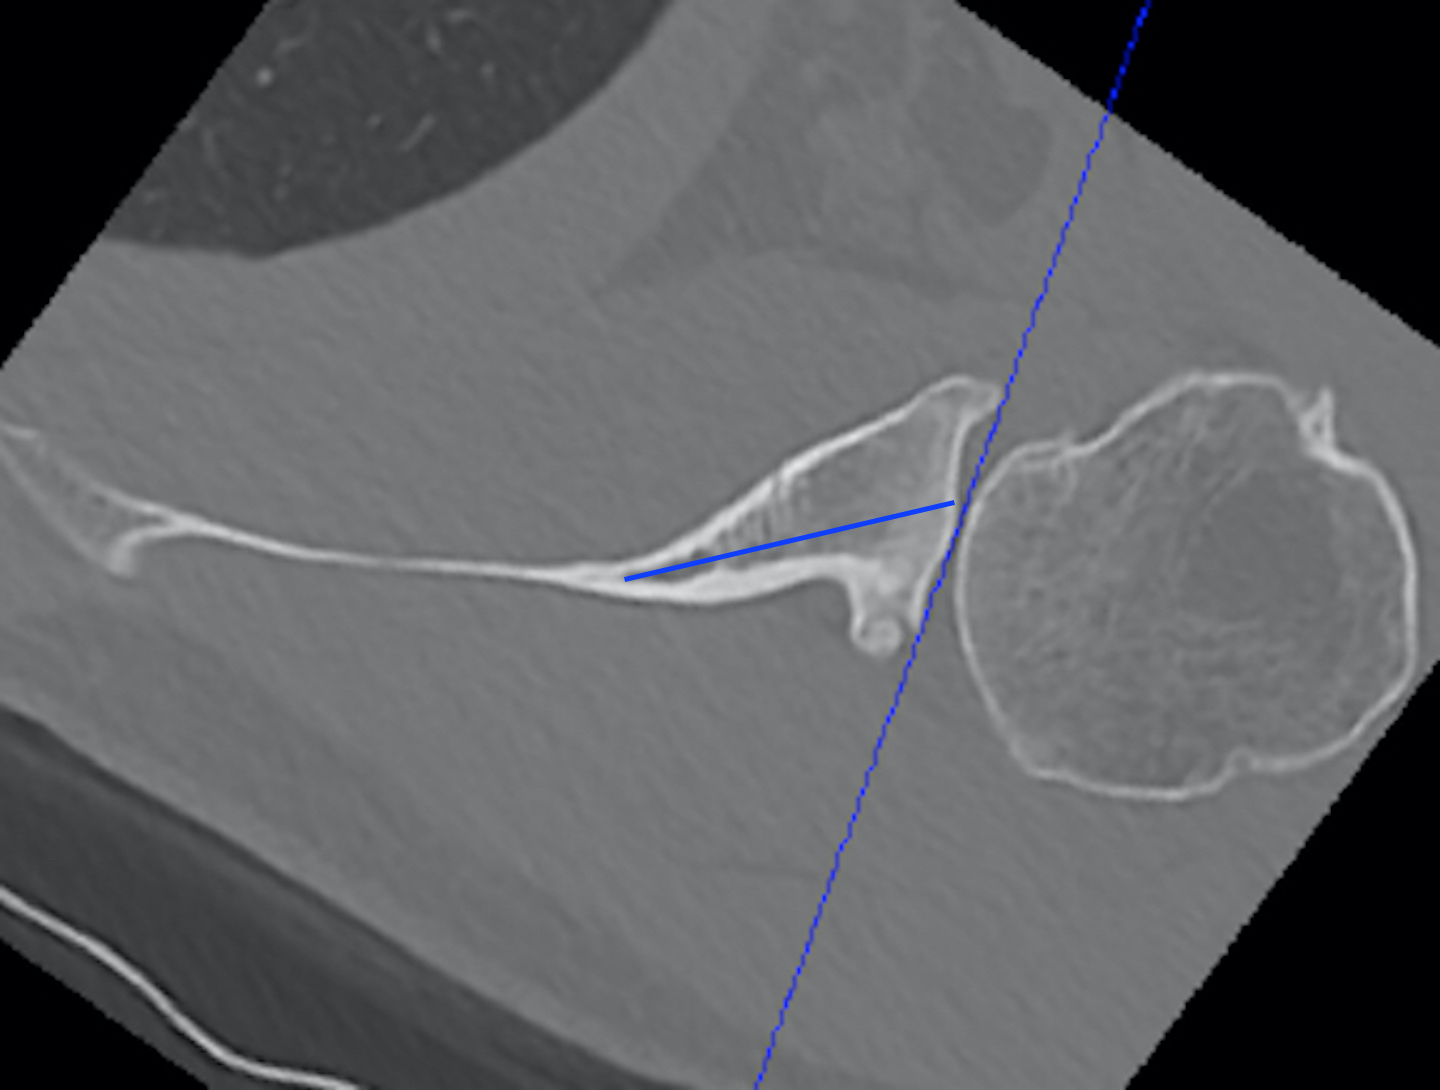

a. Friedman method

- tip of the medial border of the scapula to the midpoint of the glenoid fossa

b. Scapula body method

- intersection of the scapula body axis and the glenoid surface

- 3o difference in measurement of glenoid version between the two

- excellent reliability for both measurement techniques

c. Glenoid vault method

- tip of scapula vault to centre of glenoid